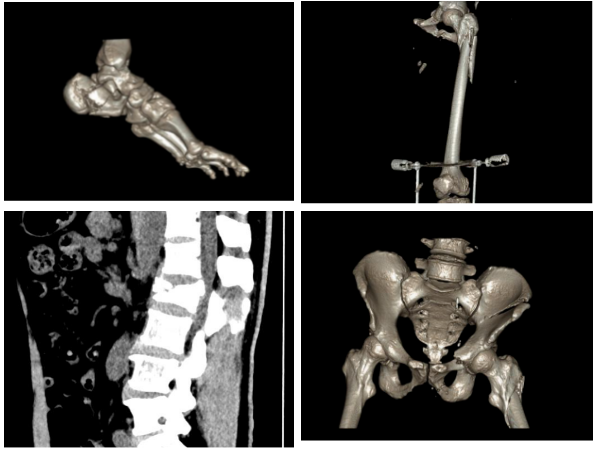

54岁的车先生不慎从6米高处坠落,身上多处严重受伤甚至一度昏迷。120送至我院急诊科时,通过CT检查发现,车先生全身多处骨折(腰2椎体爆裂骨折,左髂骨翼、左髋臼骨折、左股骨粉碎性骨折、左跟骨粉碎性骨折)

等到车先生的情况稳定后,黄刚主任立即组织科内疑难病例讨论及多学科会诊,结合车先生具体情况,制定了分期手术的方案,一期处理骨盆骨折及股骨近端骨折,二期处理腰椎骨折及跟骨骨折。

经过前期细致的准备,手术如期进行。我院骨伤科、普外科团队共同努力,麻醉科、手术室密切配合,一期手术取得了成功,骨盆骨折及股骨粉碎性骨折即刻获得复位及稳定,术后转至重症监护室(ICU)监护,2天以后车先生转回普通病房,生命体征平稳。

二期手术按原计划如期进行, 腰椎及跟骨手术过程顺利,出血少,骨折解剖复位,内固定精准牢靠。